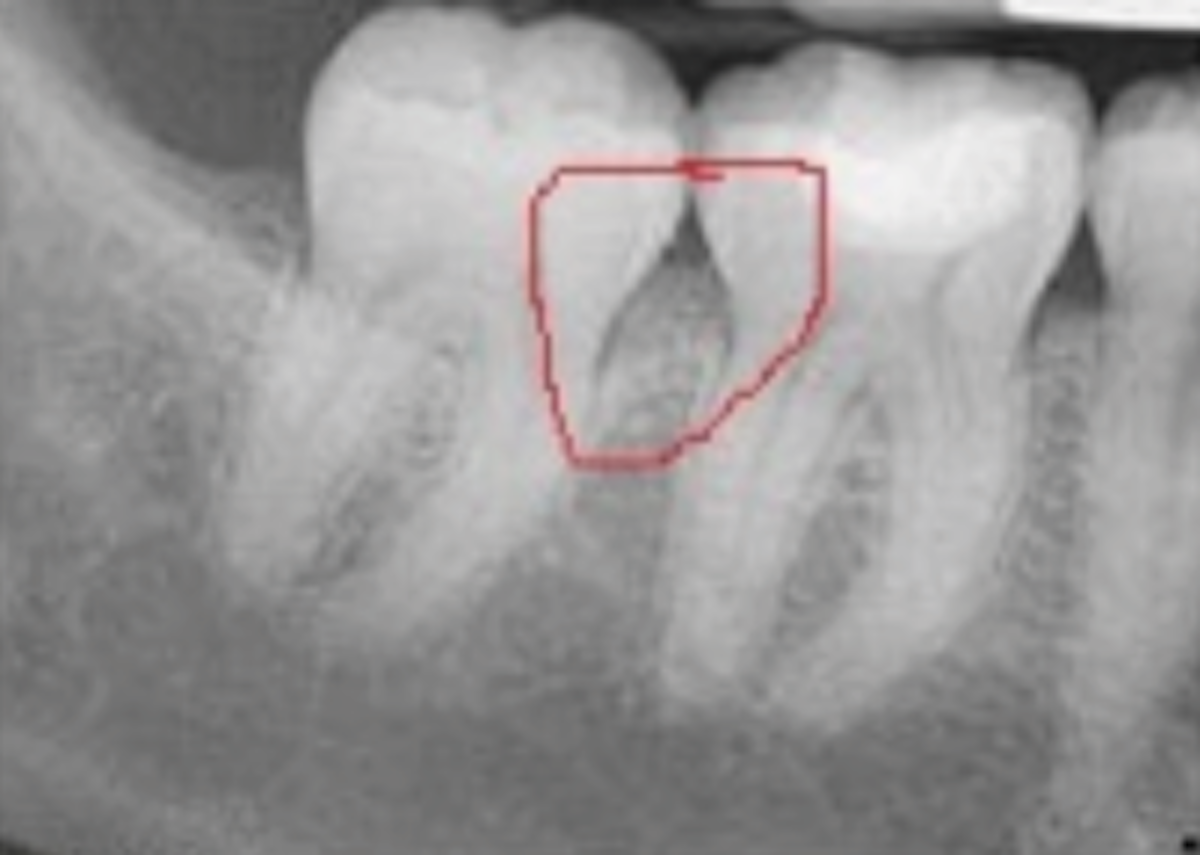

Get Periodontal Bone Loss Images. In periodontal disease, not only does the bone that supports the teeth, known as alveolar bone, reduce in height in relation to the teeth, but the morphology of the remaining alveolar bone is altered. Bone loss is most commonly associated with the following diseases:

Inflammation and bone loss are hallmarks of periodontal disease (pd). Horizontal bone loss is the most common pattern ol bone loss in periodontal disease. It can normally be prevented through good oral hygiene.

Radiographic indication of interproximal bone loss occurs when the distance between the cej and the alveolar the percentage of subjects with periodontal bone loss was computed for each age bracket. Title radiographic alveolar bone loss in patients. Accumulated evidence demonstrates that pd involves bacterially derived factors. The bacteria responsible for periodontitis can enter your bloodstream through gum tissue, possibly affecting other parts of your body.